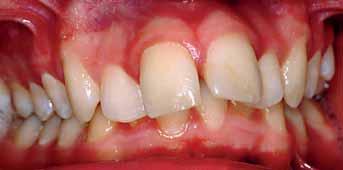

The patient had moderate Class II skeletal pattern with average Frankfort-mandibular planes angle and lower anterior face height. There was no facial asymmetry and the lips were incompetent with the lower lip trapped at rest behind the upper central incisors (Figure 1).

The oral hygiene was fair but needed improvement prior to orthodontic treatment. All teeth from the left permanent second molar to the right have erupted in both the upper and lower arches. The patient had carious lesions in both upper first molars, upper left second molar and lower left first molar. The maxillary arch was spaced with a midline diastema. Furthermore, there was mild lower labial segment crowding (4mm). The incisor relationship was Class II division 1, the overjet was 12 mm whereas the overbite was increased and complete to the palate

and causing trauma to the palatal mucosa. The centrelines were coincident and the buccal segment relationship was 1/2 unit Class II on both sides (Figure 2).

The treatment of the case was planned in stages. Stage one consistedof improving the oral hygiene of the patient and management of all carious lesions and assesses the compliance and attitude of the patient towards orthodontic treatment. The next stage involved the reduction of the overbite. The patient presented with a deep overbite that was causing damage to the palatal mucosa (Figure 2). This was achieved with an anterior bite plane removable appliance and bonding of the lower arch. This appliance will free the occlusion of the buccal segment teeth and if worn consistently, will “passively” limit further eruption of the incisors but allow the lower premolars to erupt, thus reduce the increased overbite (Figure 5).